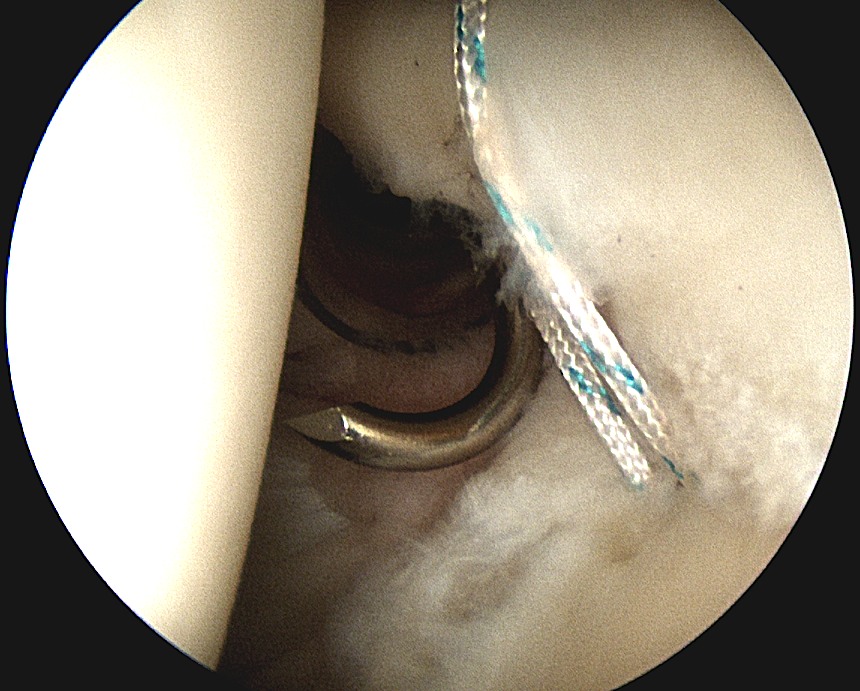

4. Dfficult posterior anchors

Camera through anterior / anterosuperiorlateral portal

A. Place anchor through posterior portal

- does not always give good angle

B. Trans infraspinatous Portal